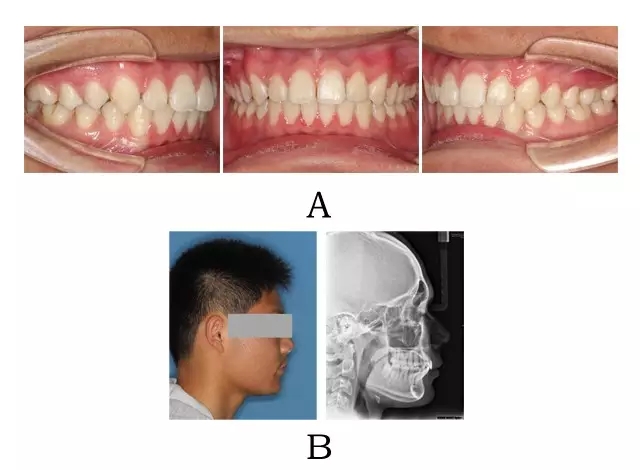

圖 4-4:混合 II 型突面畸形臨床表現(xiàn)及頭顱側(cè)位影像特征。

(A)齒槽與牙列特點(diǎn) (B)側(cè)貌與影像對(duì)比

Figure 4-4. Clinical manifestation and cephalometric image for merged skeletal and mandibular positional prognathism (Type II). (A) Alveolar and dentition specifics. (B) Facial profile and radiographic image.

一、臨床表現(xiàn)

面型輕度前突,面下高度不足伴有深頦唇溝。口內(nèi)表現(xiàn)上頜嚴(yán)重骨性前突,上前牙過度代償(內(nèi)傾),下頜后退,嚴(yán)重深覆合深覆蓋及深 Spee曲線。